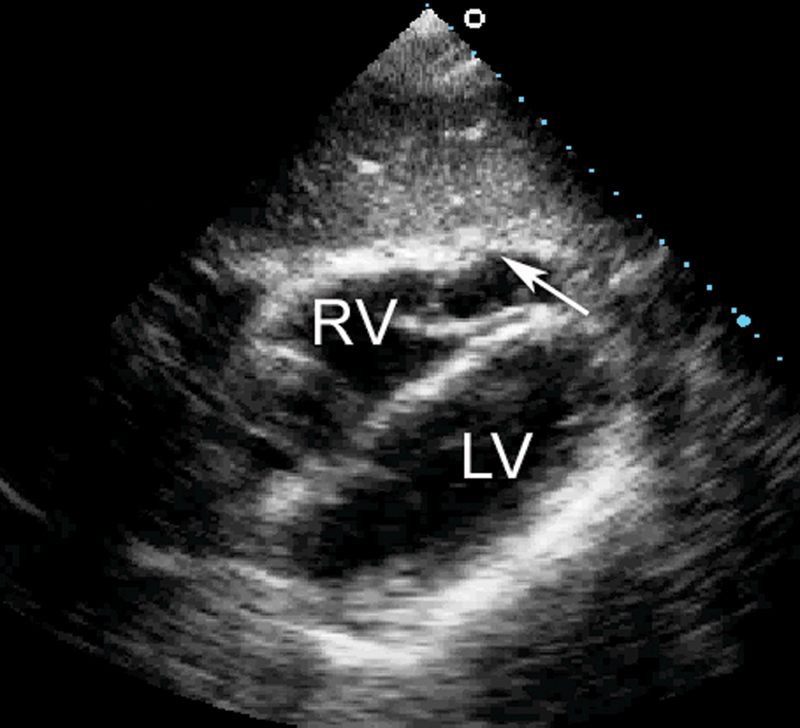

فحوصات تشخيصية لبعض امراض القلب والشرايين التاجية